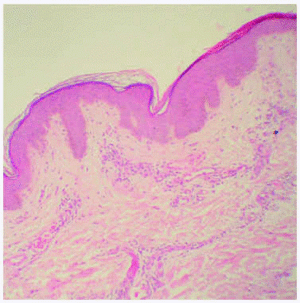

Se realizó una biopsia de una de las lesiones cutáneas cuyo estudio histológico mostró la presencia de vasos dilatados en el plexo vascular superficial de la dermis papilar. A mayor aumento se observaban abundantes vacuolas en el citoplasma de las células endoteliales (fig. 4). Todos estos hallazgos eran compatibles con angioqueratoma corporis diffusum. Se realizó un estudio analítico con hemograma y bioquímica, que incluyó las funciones renal y hepática, con valores dentro de los límites normales. Se evaluaron, además, los oligosacáridos en la orina que resultaron normales y se descartaron las glucoproteinosis (α y β -manosidosis, fucosidosis, aspartilglucosaminuria y sialidosis), gangliosidosis GM1 tipo 1, gangliosidosis GM2 tipo Sandhoff, galactosialidosis, enfermedad de Schindler y glucogenosis II, III y VI. El análisis enzimático en fibroblastos mostró unos valores normales para β -galactosidasa, hexosaminidasa y N-acetilneuraminidasa, con valores claramente disminuidos para α -galactosidasa (3,2 nmol/h/mg prot. frente a 56,5 del control), por lo que fue diagnosticado de enfermedad de Fabry. La madre del paciente presentaba unos valores en el rango de portadora (162 nmol/min/g de prot. frente a 1.144 del control). El análisis genético confirmó el estado de portadora y por lo tanto la heterozigosidad para esta enfermedad. Se practicó una biopsia renal cuyos hallazgos fueron compatibles a los referidos en la enfermedad de Fabry (fig. 5).

Fig. 4.--Detalle anatomopatológico de las lesiones cutáneas que muestra vasos dilatados en el plexo vascular superficial. (Hematoxilina-eosina, x20.)